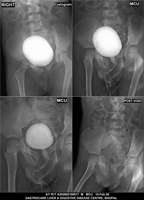

Section: URETHROGRAM

Total: 95 Cases